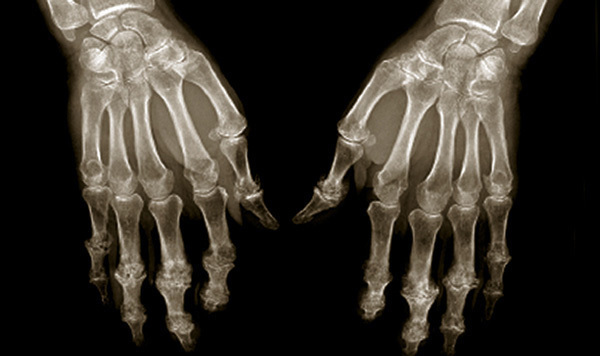

Radiographie des deux mains caractéristiques d'une arthrose digitale avec un pincement des interlignes articulaires et une ostéophytose.